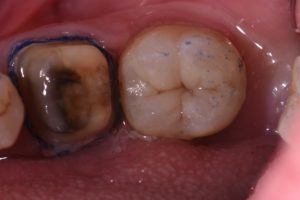

Making things look ka te pai with #GC #EssentiaU